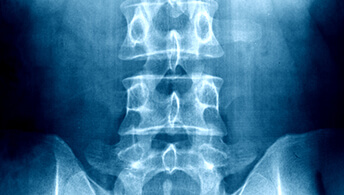

The management of pain is not only about treating the symptoms, but also about finding the underlying causes of pain and treating them through evidence-based and personalized treatment approaches. Whether you are experiencing muscle injuries and joint issues, nerve conditions and post-surgical pain, our experts assess your individual needs to offer specific, long-term pain relief.

- Advanced imaging and diagnostic equipment to make accurate assessment

- Chronic back pain